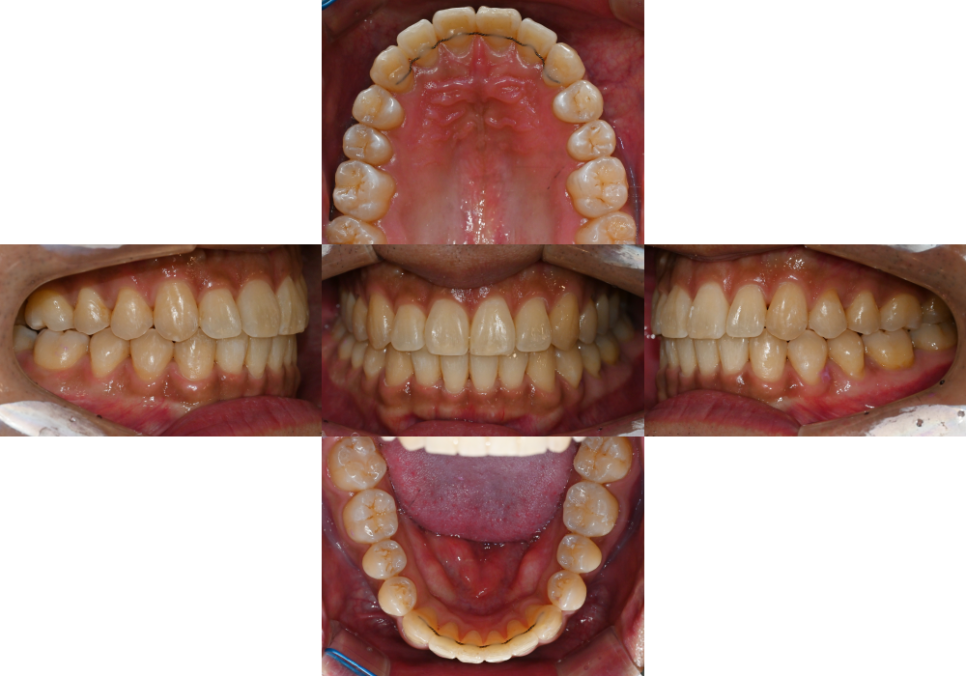

| 4. 완료

25.01.31

총 14개월의 치아 교정 결과

위아래 맞물림이 자연스러우면서도

위아래 정중선이 알맞게 맞는 것을

확인할 수 있습니다.

실제 치열을 보았을 때도

정중선이 딱 맞는 것을 볼 수 있으며

이후 치열이 다시 되돌아가지 않도록

유지 장치를 부착한 것을 볼 수 있었습니다.